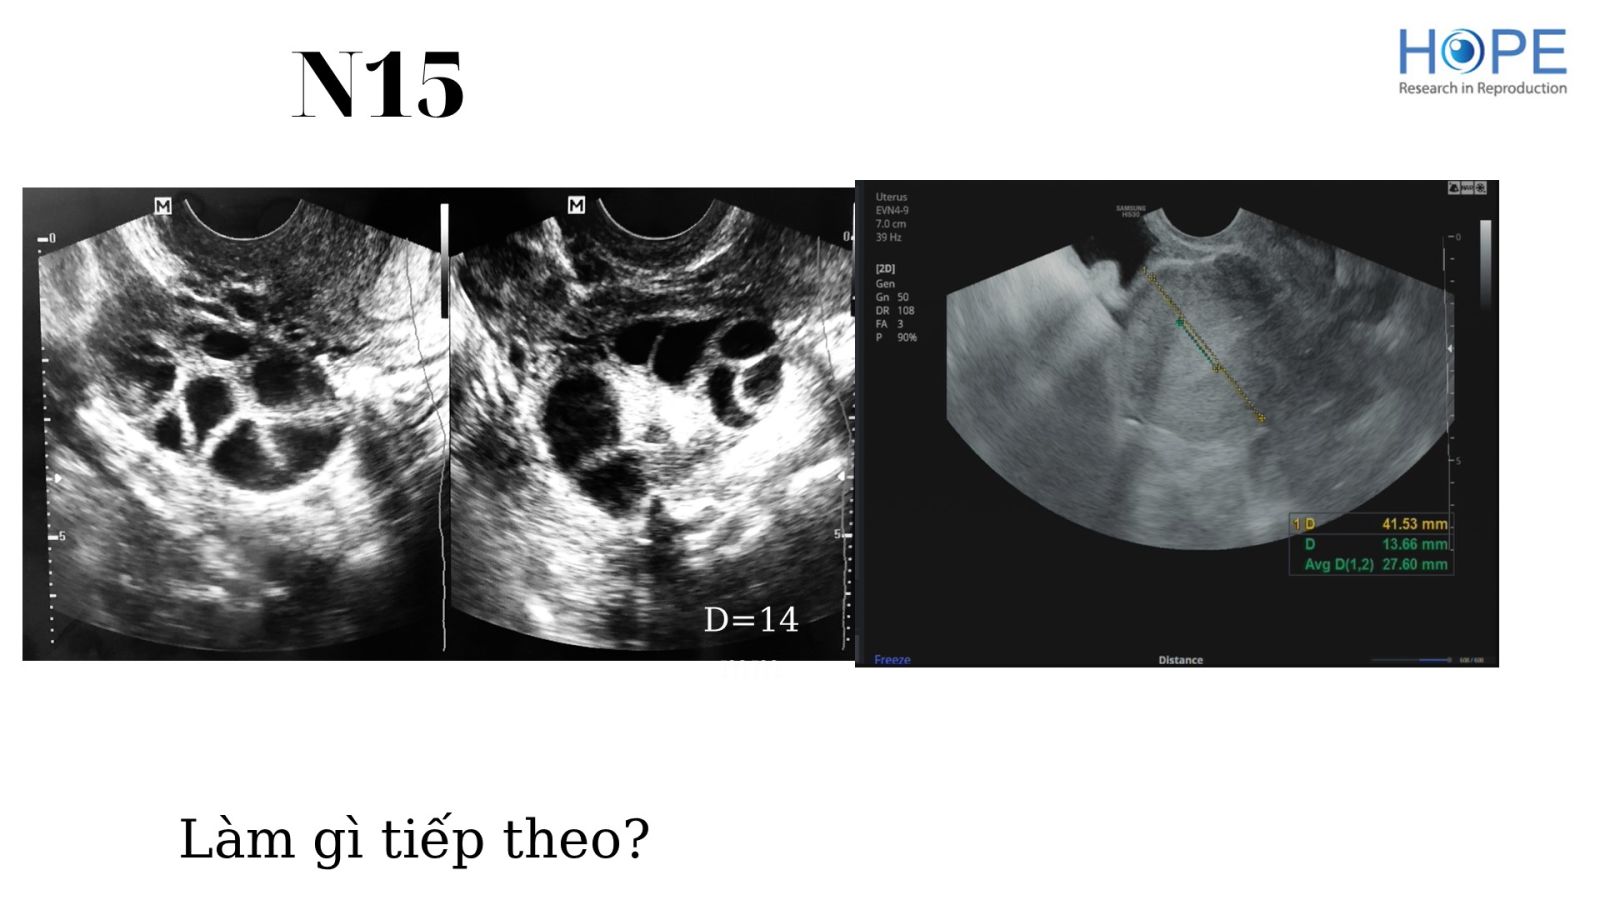

Các phác đồ kích thích buồng trứng nhẹ để IUI –  cách theo dõi kích thích buồng trứng

BS Lê Thị Hà Xuyên - IVFMD Phú Nhuận